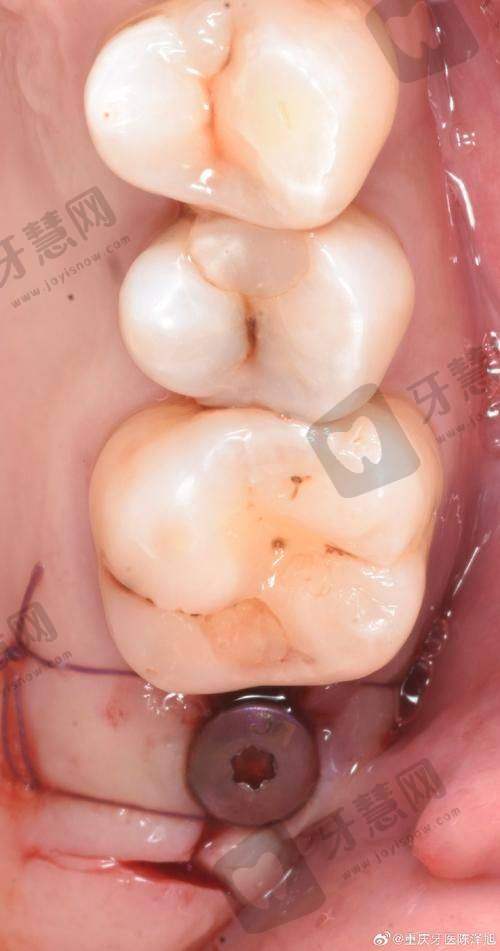

孟岩医生:专注于单颗、多颗及全口种植领域,在美学种植修复方面造诣颇深。擅用动态导航技术规划种植路径,针对半口/全口缺牙患者,常采用ALL - ON - 4/6即刻负重技术,实现当天戴牙的快速修复。曾为商务人士采用该技术,当天种牙当天就能吃东西。

李刚医生:作为“立得用”种植体系的实践者,在即刻种植与即刻修复领域有独到见解。主攻半口/全口牙缺失的即刻功能重建,通过术前数字化模拟设计,拔牙后同步完成种植体植入,术后肿胀轻微,受上班族患者青睐。

刘成医生:从事口腔临床工作10余年,完成种植病例近万颗。擅长“立得用”种植牙体系、即刻种植、即刻负重等新技术,对疑难种植病例经验多。对待患者如亲人,耐心解答疑问,术后还关心患者修复情况。